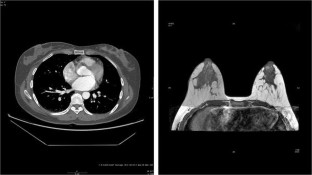

Fig. 1

Fig. 2

Fig. 3